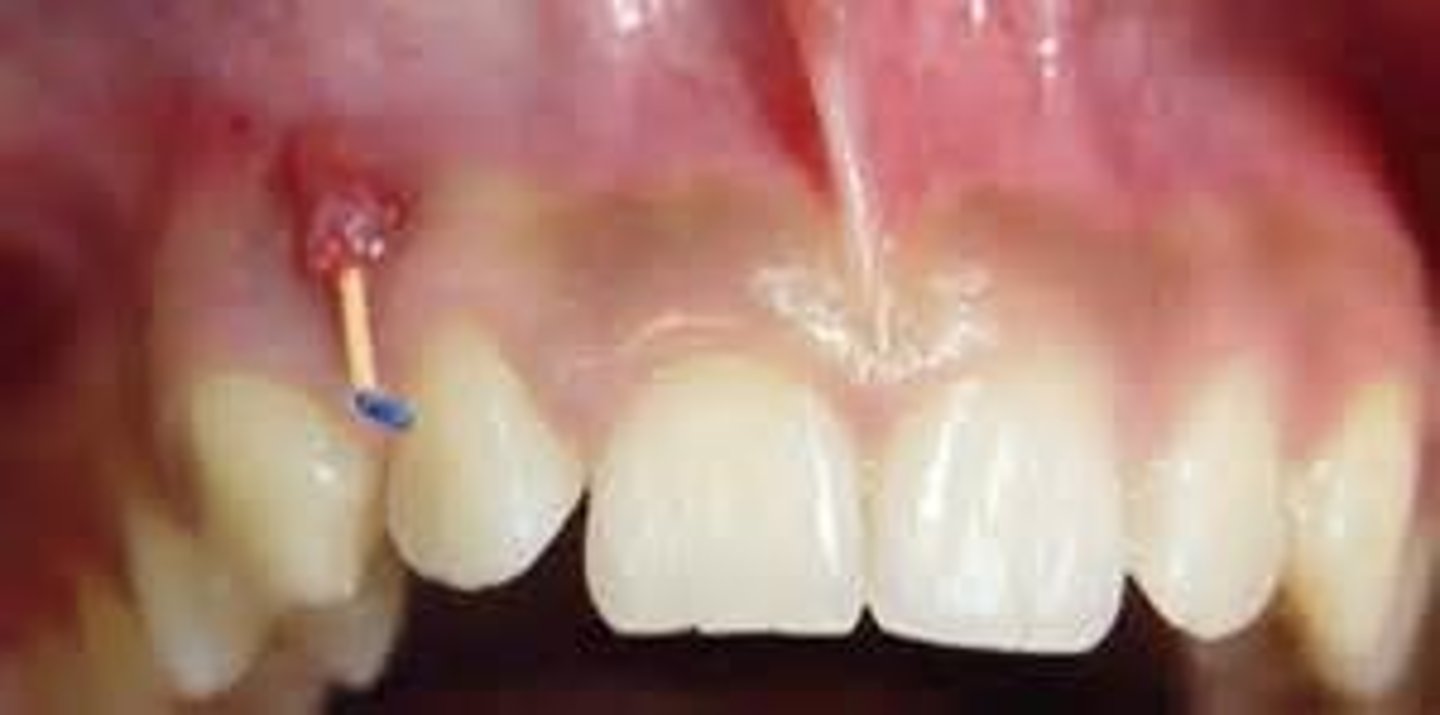

What is Pericoronitis associated with?

Third molars

What are the symptoms of Pericoronitis?

Pain + swelling

What X-ray finding is associated with Pericoronitis?

Loss of cortical outline